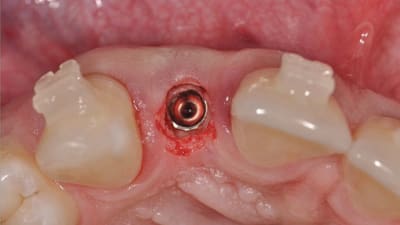

Case Reports Implantology Options for the Esthetic Zone Using the Immediate Restoration Procedure: Observational Data of 15 Years and 5000 Implants By Paul S. Petrungaro, DDS May 01, 2017 18 min read